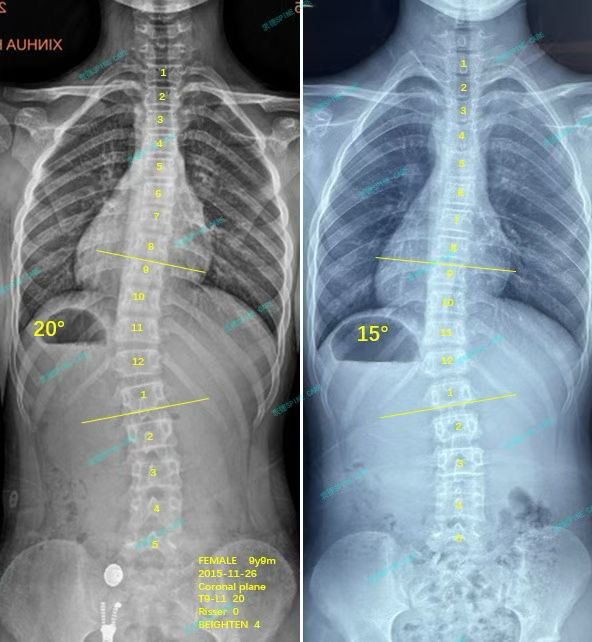

我是彤彤,10岁女孩训练3个月后胸弯降至15度,腰线基本对称~

案例主人:彤彤 发现侧弯年龄:10岁 侧弯情况:Cobb角度20度

坚持了三个月过后,发现我的侧弯顺利从20度降低到了15度,妈妈和我都很开心,衷德是正确的选择!后期我还会继续努力!

After persisting for three months, I found that my lateral bending had been successfully reduced from 20 degrees to 15 degrees. My mother and I were very happy. Zhongde was the right choice! I will continue to work hard in the later period!